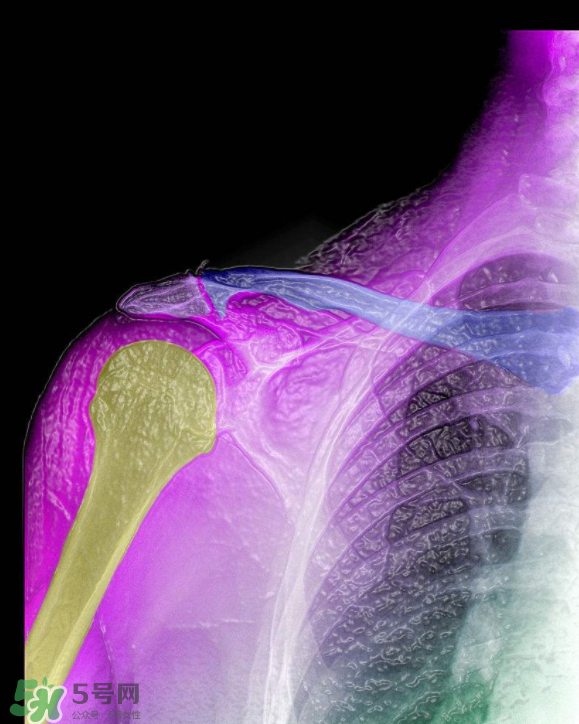

1、骨刺,多發(fā)于活動(dòng)度最大、負(fù)重最多的頸椎、腰椎、骶椎、膝關(guān)節(jié)、足跟等部位。隨著年齡的增長(zhǎng),人的關(guān)節(jié)軟骨彈性會(huì)銳減,軟骨膠原纖維顯露,關(guān)節(jié)中部活動(dòng)時(shí)極易磨損,其外周軟骨面便代謝性增殞肥厚,最后骨化形成骨刺。職業(yè)性持久用力、長(zhǎng)期被迫體位不良、慢性或機(jī)械性刺激、跌打損傷等是誘發(fā)骨刺形成的原因。

2、骨刺患者一旦增生的骨刺刺激鄰近組織和壓迫神經(jīng)根時(shí),就會(huì)出現(xiàn)局部或放射性骨刺的疼痛。主要表現(xiàn)為上肢麻痹、肩背疼痛、頸項(xiàng)僵硬、頭暈、胸悶不舒、心悸心慌、坐骨神經(jīng)痛、下肢麻痹痛、怕冷、膝關(guān)節(jié)腫痛、上下樓梯困難、不能下蹲等一系列骨刺的病理變化。如不及時(shí)治療,就會(huì)使骨刺的病情加重,增加治療難度。因此,這些都是骨刺形成的原因。